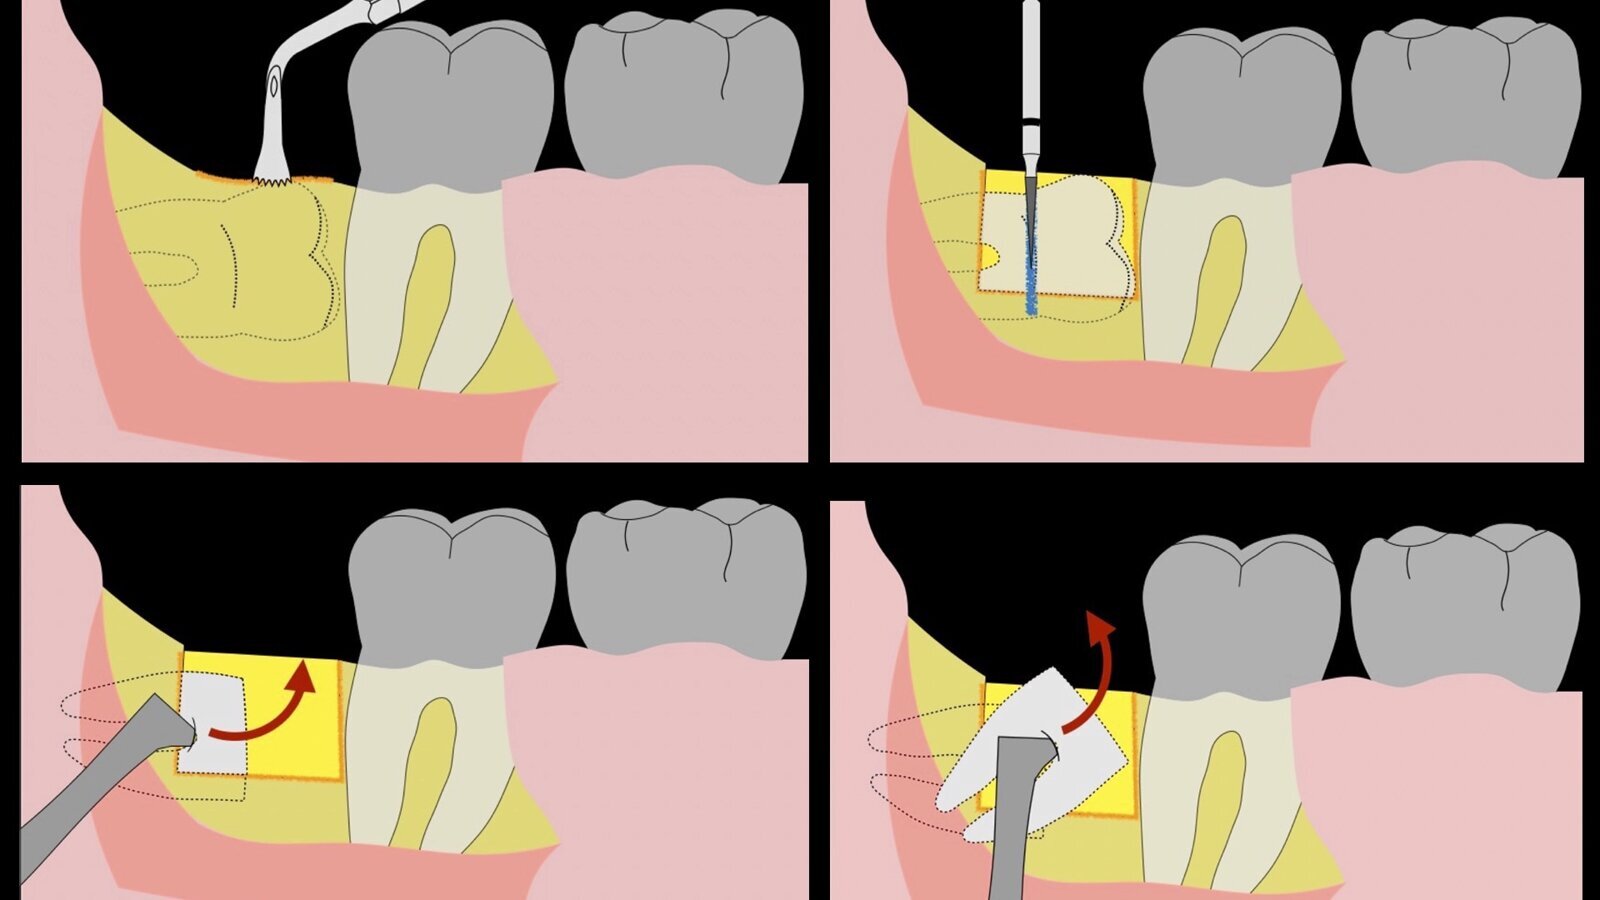

Figura 4. Demarcación de la zona de osteotomía con insertos de corte recto y/o angulado a nivel oclusal. Vista frontal (a). Vista oclusal (b).

Figura 5. Fractura y eliminación oclusal del fragmento óseo de la porción coronal oclusal.

Figura 6. Demarcación y fractura de la zona de osteotomía a nivel vestibular con inserto aserrado recto y/o angulado.

Figura 7. Eliminación del fragmento vestibular.

Figura 8. Odontosección mediante fresa de alta rotación y/o inserto de corte de piezoeléctrico. Posteriormente se procede al ensanchamiento del espacio pericoronario con el periótomo de piezoeléctrico para facilitar la avulsión de la pieza dentaria.